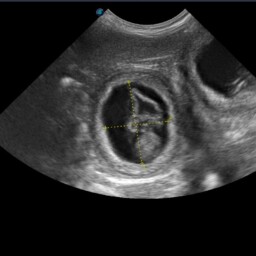

• Biometria płodowa (wyznaczanie terminu porodu na podstawie pomiarów struktur płodowych)